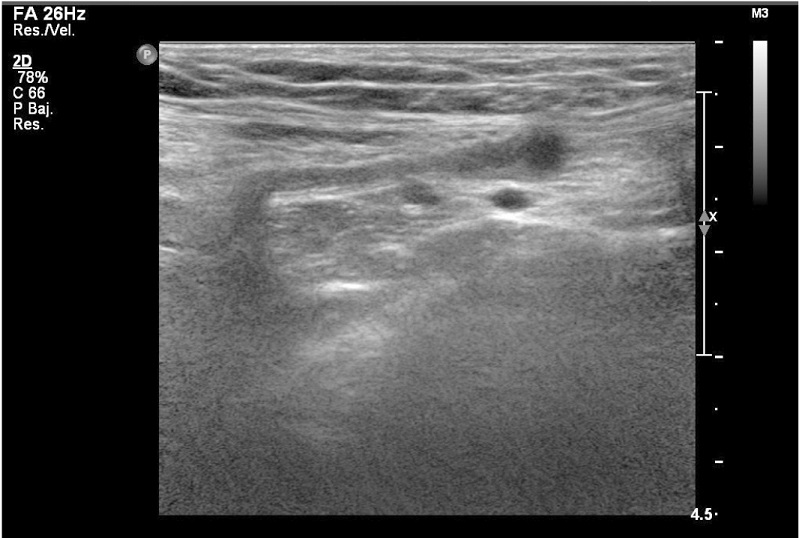

Ante la sospecha de hernia inguinocrural, se derivó a la paciente al hospital para valorar indicación quirúrgica y se realizó ecografía abdominal. En la ecografía se observó una imagen de aspecto tubular hipoecogénica alargada en región medial a los vasos iliofemorales derechos de 3,5 cm x 0,7 cm x 0,4 cm de diámetro (figura 1), dolorosa a la presión con el transductor, que en estudio Doppler mostró algún foco mínimo de vascularización periférica.

El diagnóstico principal suele hacerse por ecografía, donde es común visualizar quistes de menos de 3 cm, con contenido anecoico y sin señal Doppler, que pueden tener forma de coma redondeada o tubular.